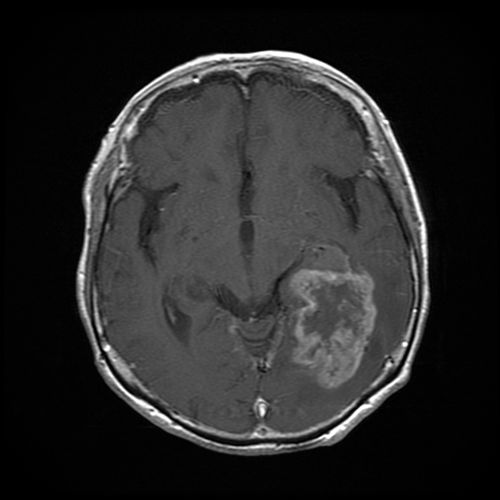

悪性神経膠腫の造影MRI- 神経膠腫 (悪性神経膠腫/境界悪性神経膠腫)

主に頭蓋内 (頭蓋骨の内がわ)にできる病変を“脳腫瘍”と呼びます。原発性脳腫瘍は、脳の細胞・脳を包む膜・脳から出る神経からできると言われており、150種類以上に分類されています。また、乳癌・肺癌といった病気が脳に転移する転移性脳腫瘍もあります。診察後にCT・MRI検査などを行い、経過観察をするか手術などをするか決めていきます。

悪性腫瘍の場合は、手術して病理診断 (手術で摘出した病変がどういった腫瘍であるか診断する)後に、患者さん本人の状態をみて 化学療法・放射線療法を行います。

良性腫瘍の場合は、たとえ良性であっても手術後に再発したりする場合もあるので、外来で経過観察をしていきます。